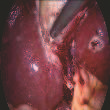

Phase recognition plays an essential role for surgical workflow analysis in computer assisted intervention. Transformer, originally proposed for sequential data modeling in natural language processing, has been successfully applied to surgical phase recognition. Existing works based on transformer mainly focus on modeling attention dependency, without introducing auto-regression. In this work, an Auto-Regressive Surgical Transformer, referred as ARST, is first proposed for on-line surgical phase recognition from laparoscopic videos, modeling the inter-phase correlation implicitly by conditional probability distribution. To reduce inference bias and to enhance phase consistency, we further develop a consistency constraint inference strategy based on auto-regression. We conduct comprehensive validations on a well-known public dataset Cholec80. Experimental results show that our method outperforms the state-of-the-art methods both quantitatively and qualitatively, and achieves an inference rate of 66 frames per second (fps).